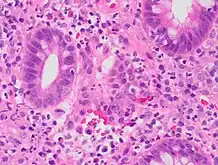

| A micrograph demonstrating cryptitis, a microscopic correlate of colitis. H&E stain. | |

An important investigation in the assessment of colitis is biopsy for histopathology. A very small piece of tissue (usually about 2mm) is removed from the bowel mucosa during endoscopy and examined under the microscope by a histopathologist. A biopsy report generally does not state the diagnosis, but should state any presence of chronic colitis, give an indication of disease activity, as well as state the presence of any epithelial damage (erosions and ulcerations).[4]

Histopathology findings generally associated with chronic colitis include:[4]

Crypt degeneration

Crypt branching and other architectural distortions

Paneth cell (pictured) or gastric metaplasia (only applies in the left colon and rectum)

Other findings include basal plasmacytosis and mucin depletion.[4] Histopathology findings generally associated with active colitis include:[4]

Neutrophilic cryptitis (neutrophils within crypt epithelium)

Crypt abscesses (luminal neutrophilic aggregates)

Gland destruction

Ulceration (seen here as absence of epithelium, and granulation tissue with many fibroblasts)